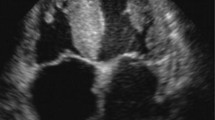

Besides, STE is useful in discerning the cause underlying the ventricular hypertrophy. Global myocardial deformation is lower in CA than in left ventricular hypertrophy. However, in patients with CA, myocardial deformation is not only globally reduced, but it is impaired mostly in the basal segments, whereas the apical contractility is preserved. This expected “apical sparing” is clearly observed on longitudinal speckle tracking [38] (Fig. 1).

Longitudinal deformation by 2D-strain shows severe impairment of global longitudinal deformation (− 11.9%, panel A) with apical sparing due to a lower deformation in basal (green segments) compared to apical segments (blue arrows on panel C). However, the global systolic function is preserved (panel B). (From Di Bella et al. Eur Heart J Cardiovasc Imaging. 2014 Dec;15(12):1307–15, by permission of Oxford University Press) [24••]

The presence of apical sparing is defined through the visual assessment as a reduction of the longitudinal strain in the basal and middle segment relative to apical. However, apical sparing can be calculated as the Relative apical LS index (RapLSI) [39••] as follows: